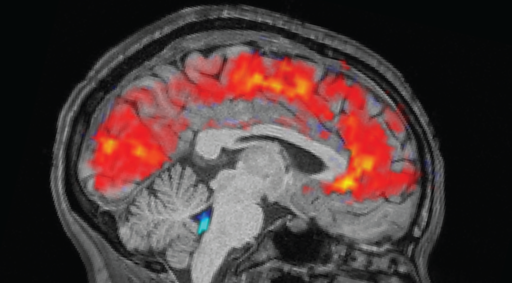

Interesting but I don’t think it’s necessarily related to neurodiversity. The article is talking about severe sleep deprivation; it suggests that the brain is attempting to conduct activities usually reserved for sleep (e.g. clearing out waste materials via cerebrospinal fluid) whilst you’re awake, resulting in those loss of concentration moments.